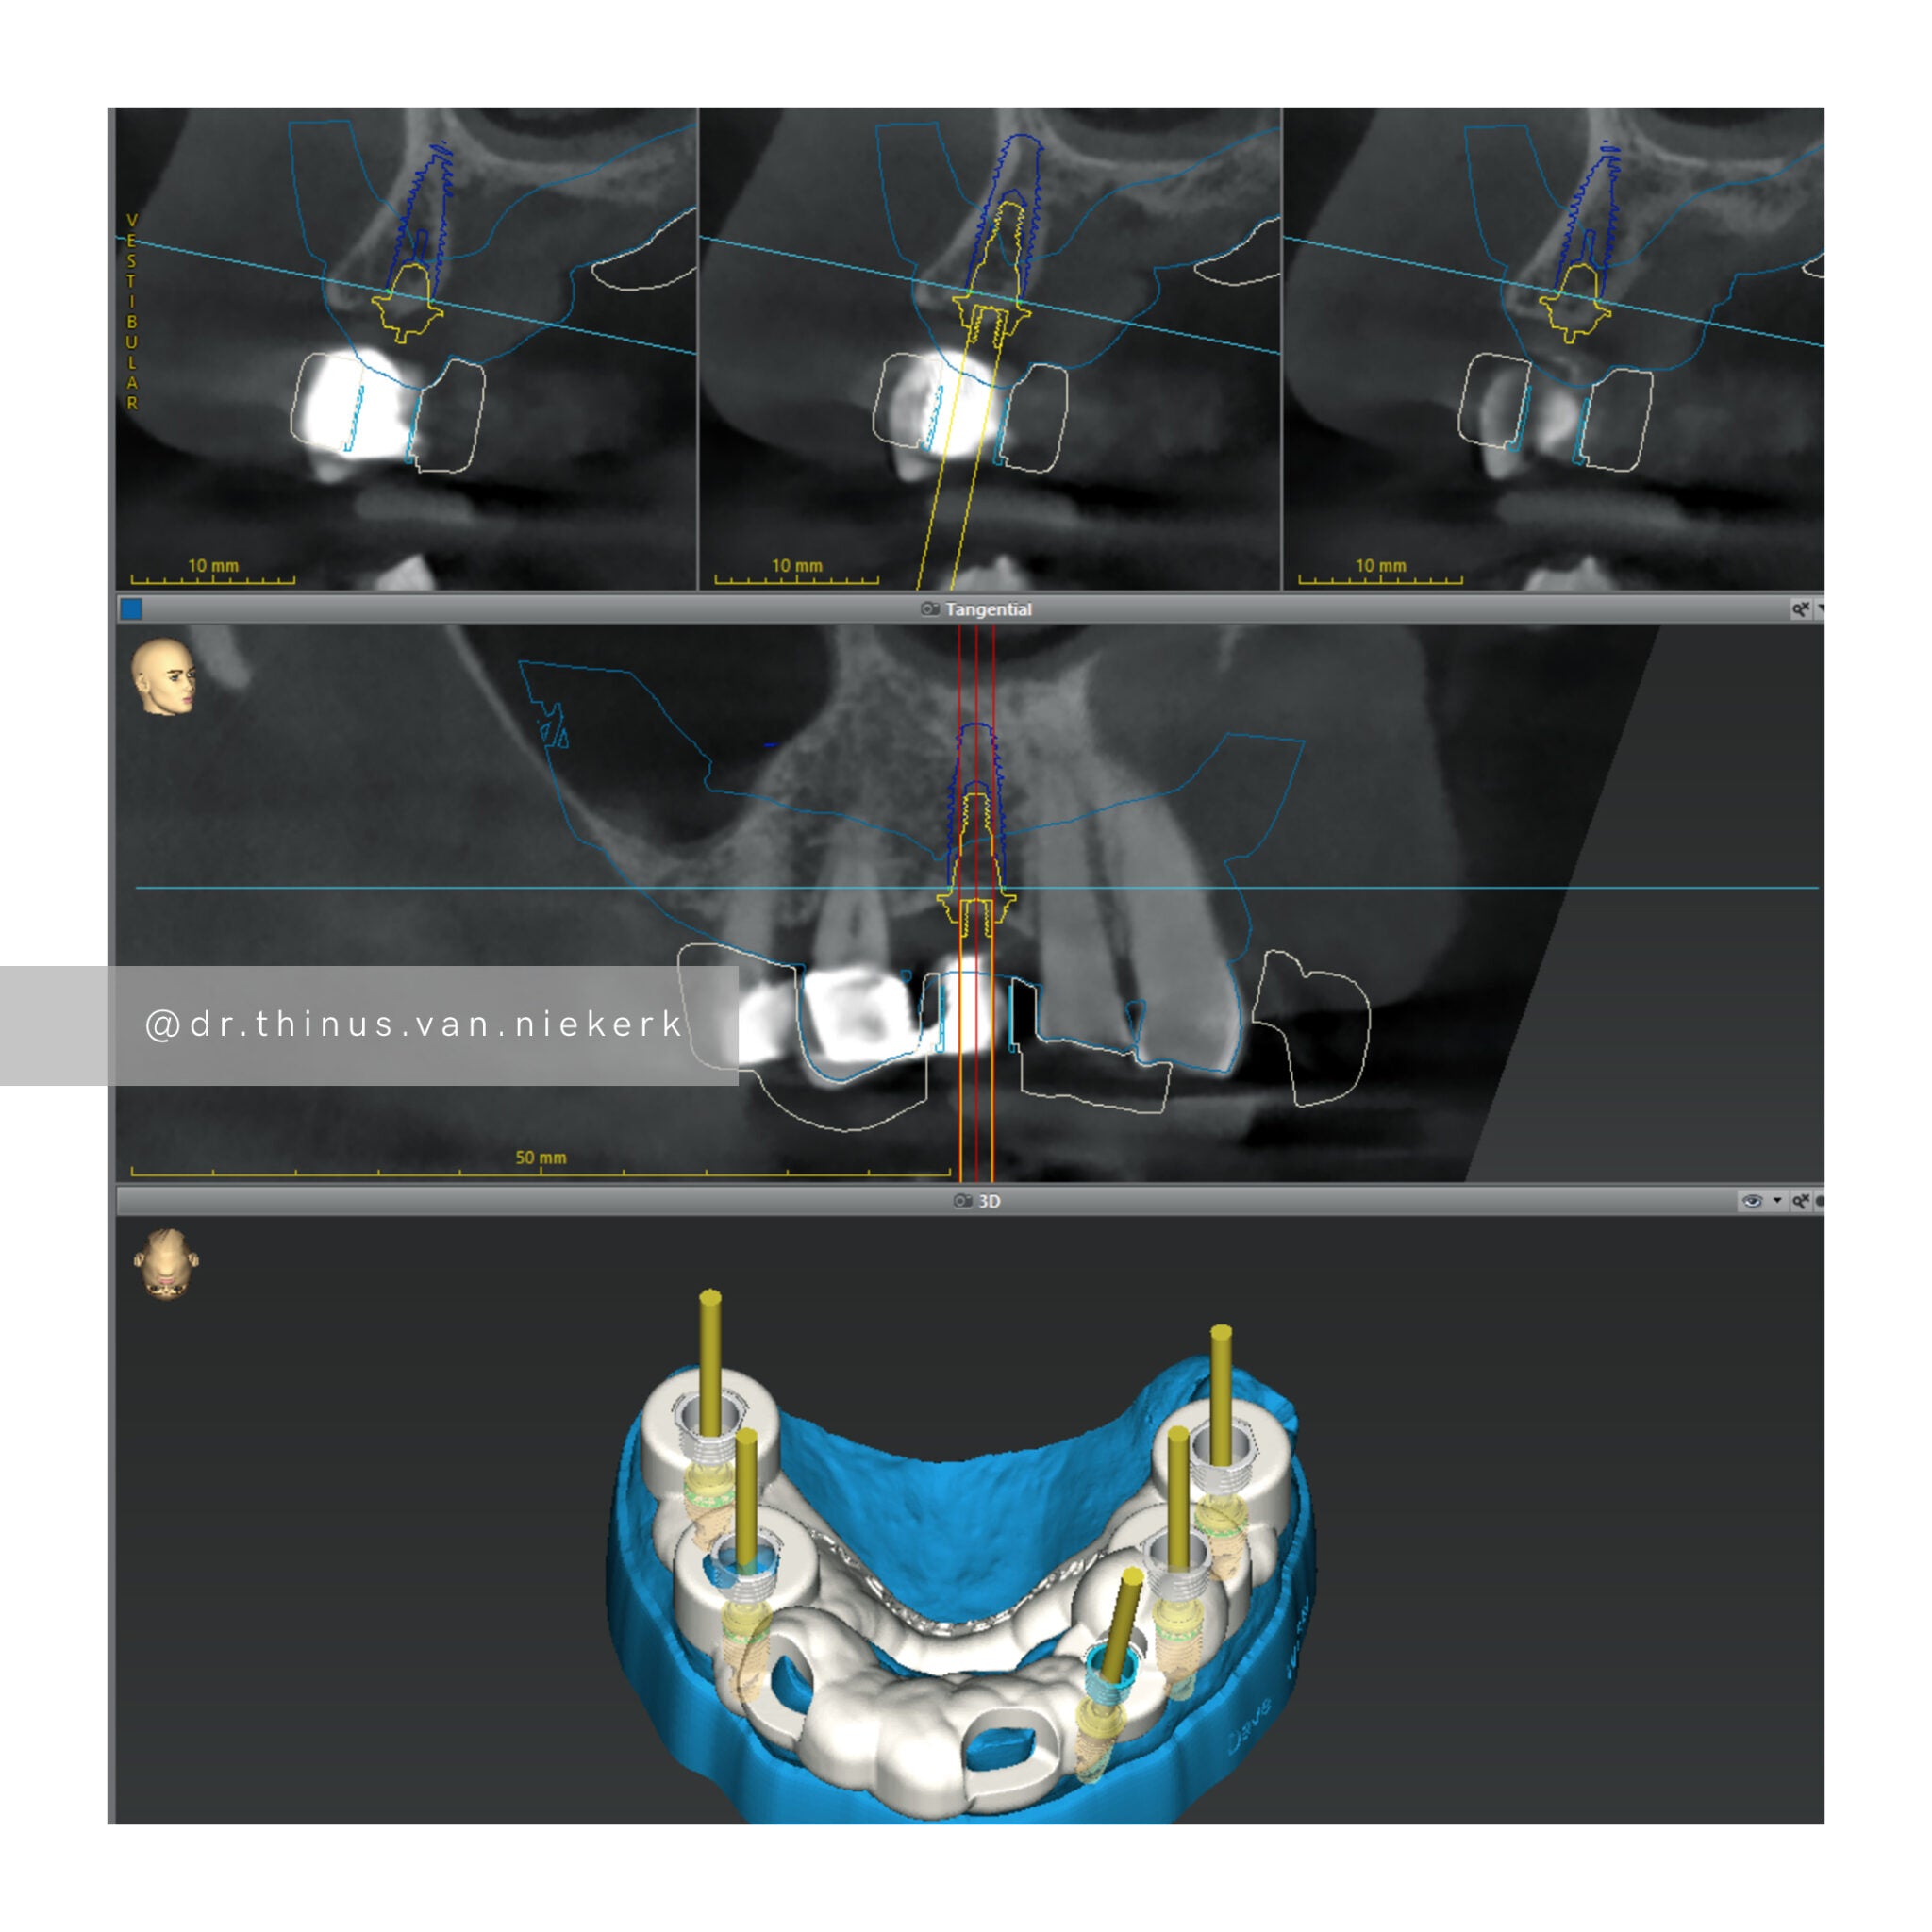

Case 1

TREATMENT OBJECTIVE

Our patient endured a long history of oral disease and associated infections. Our aim was to remove all elements of infection and disease and to restore function as quickly as possible. Six fully-guided implants were placed and immediately restored with implant-supported prosthesis in both the upper and lower jaws respectively. These were then converted to final zirconia framework prosthesis as healing and tissue remodeling allowed. The complete timeline for a treatment such as this varies from 6-24 months.

COMMENTS

This was a landmark case for our clinic – being the first fully digitally-planned upper and lower rehabilitation. This case demonstrated the power and effectiveness of digital implant-surgery planning and CAD design software. No adjustments were needed at the placement of the final lower prosthesis.